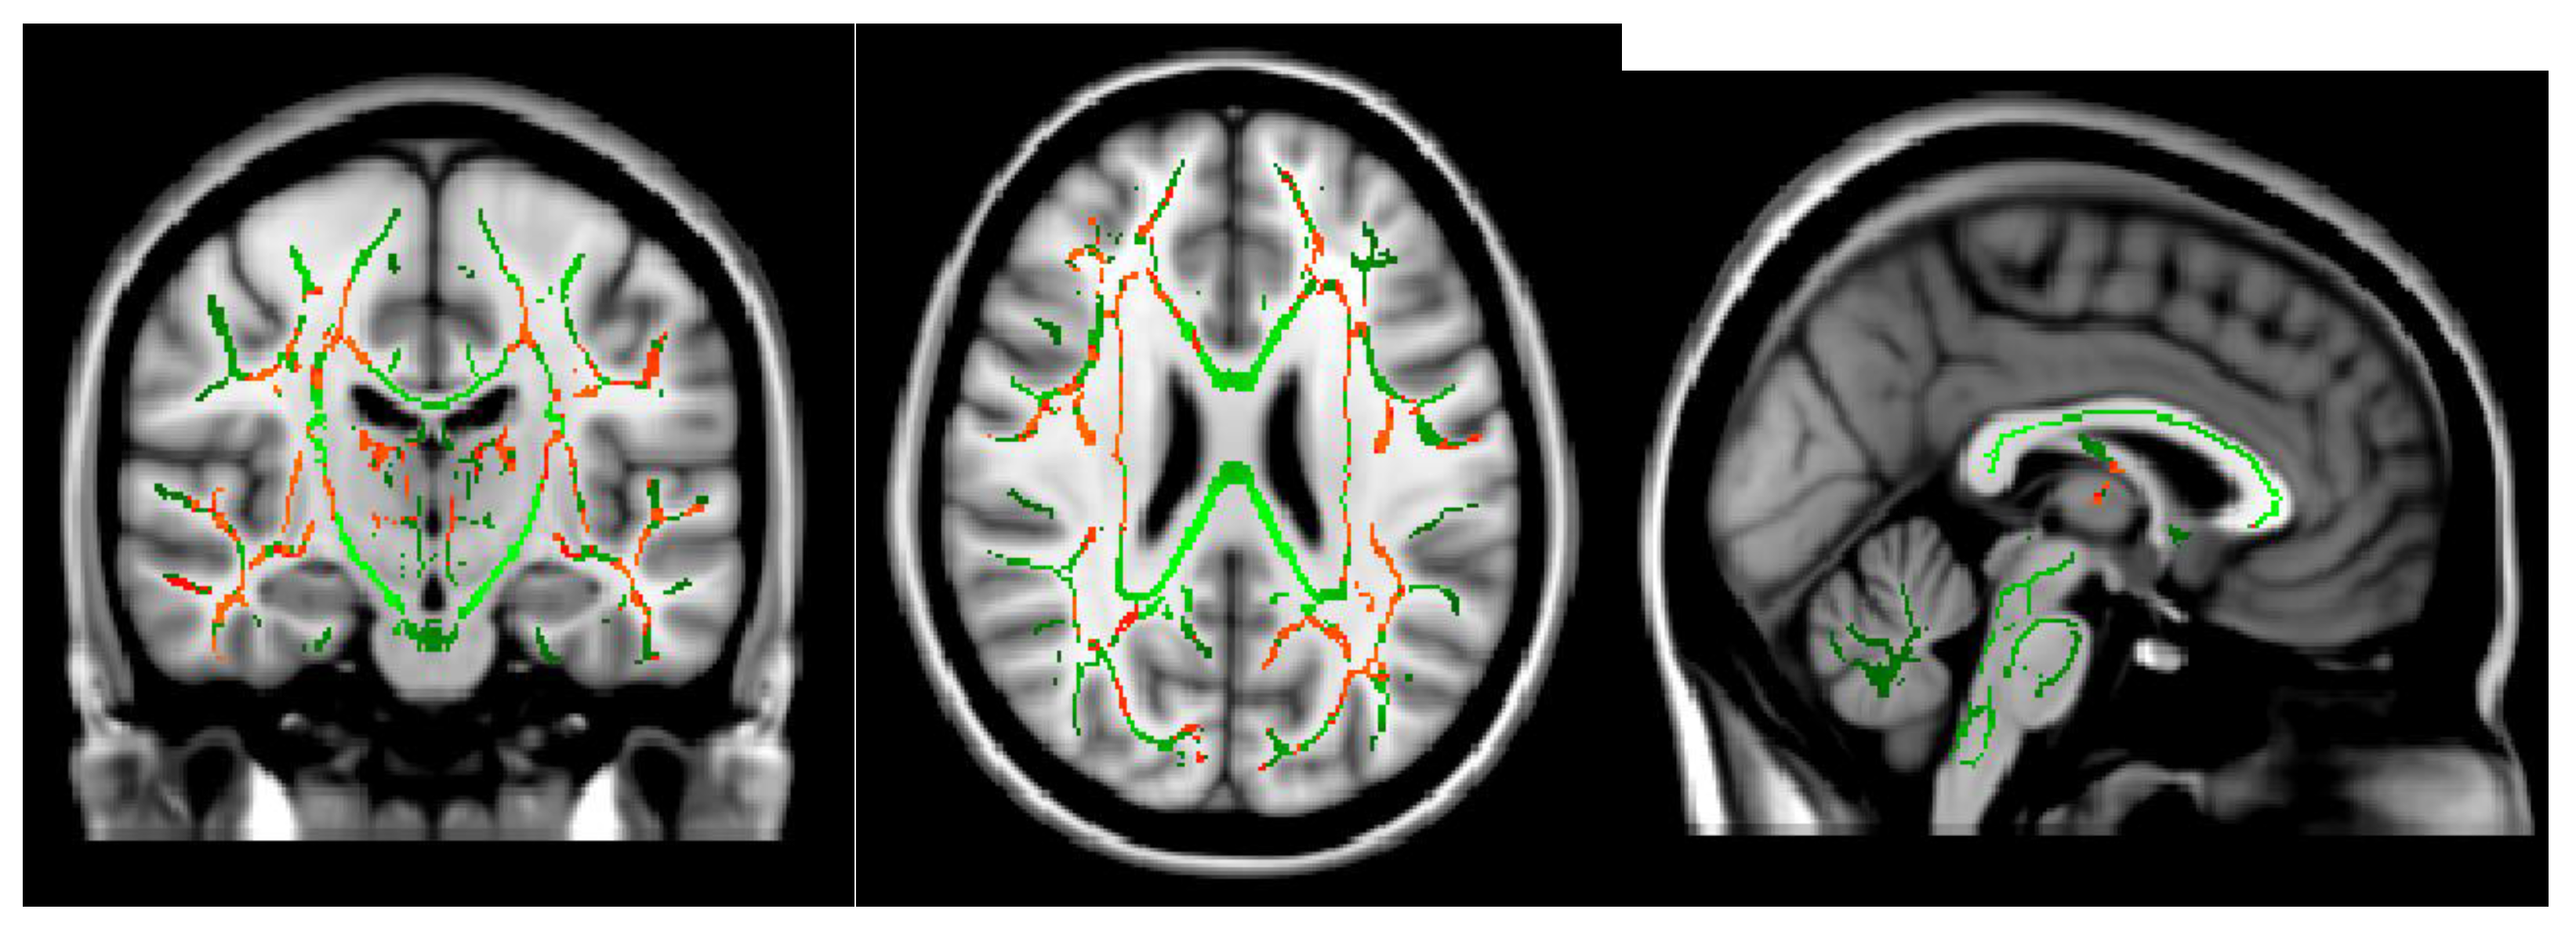

- Shibata, Y.; Ishiyama, S.; Matsushita, A. White matter diffusion abnormalities in migraine and medication overuse headache: A 1.5-Tesla tract-based spatial statistics study. Clin. Neurol. Neurosurg. 2018, 174, 167–173. [Google Scholar] [CrossRef]

- Smith, S.M. Tract-based spatial statistics. NeuroImage 2006, 31, 1487–1505. [Google Scholar] [CrossRef]